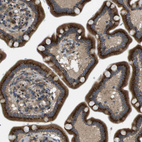

Immunohistochemical staining of human skeletal muscle shows strong cytoplasmic positivity in myocytes.